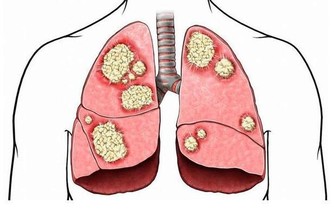

50歲的陳先生因不明原因的咳嗽去醫院就診,誰知道,做完CT檢查,竟發現是肺癌晚期。

這他難以接受甚至是惱怒,因為他每年都體檢,並且都有拍胸片,從未發現異常,為什麼現在一檢查就是肺癌晚期了?

為什麼年年體檢,卻查不出早期肺癌?

類似陳先生一樣遭遇的肺癌患者並不在少數。有人甚至將X光查肺癌稱為“最坑爹的體檢項目”,就連不少醫生也表示,用X光片篩查早期肺癌,確實不靠譜。

雖然X光片在臨床應用廣泛,但因分辨率較低,對於微小以及隱蔽部位的病灶,都不易發現到。用其篩查肺癌漏診率相當高,到用X光能夠查出時,多數已是中晚期了。

而實際上,目前醫學界公認篩查早期肺癌最有效的手段是——低劑量螺旋CT,其發現早期肺癌的敏感度是常規胸片的4~10倍,大大提高肺癌的治愈率和存活率。

但不少人擔心用CT檢查輻射大,會對身體造成傷害,實際上肺癌篩查用的不是CT的常規劑量,其射線量僅為普通CT的1/6,不必過於擔心輻射的問題。